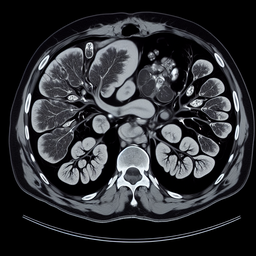

Магнітно-резонансна томографія (МРТ) селезінки — це неінвазивний метод дослідження, який дозволяє отримати детальні зображення органу. МРТ використовує потужні магнітні поля та радіочастотні імпульси для отримання зображень внутрішніх структур без використання рентгенівського випромінювання.

3. **Комплексність**: Дозволяє оцінити не тільки селезінку, але й суміжні органи та структури.

- Виявлення причини гепатоспленомегалії (збільшення печінки та селезінки).

- Діагностика травм та розривів селезінки.

- Оцінка аномалій або судинних порушень.